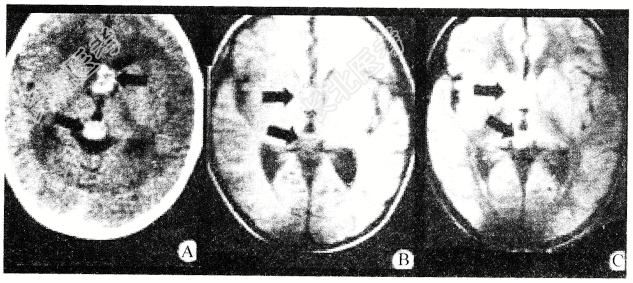

- 多项选择题松果体区肿瘤(如图所示)的临床表现是

A、出现眼球上视不能

B、易发生梗阻性脑积水,所以颅内压增高出现的早

C、可出现性早熟

D、耳鸣、耳聋

E、癫痫发作常见